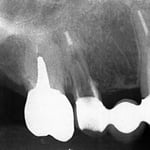

左図を拡大するとよくわかりますが、矢印の部分に確かに破折線がみえます。抜歯宣告を受けて当院を受診された方ですが、これは抜歯にはなりません。

このように、ヒビが見えるだけで、抜歯→インプラントとなるケースが、多くみられるようになってきました。